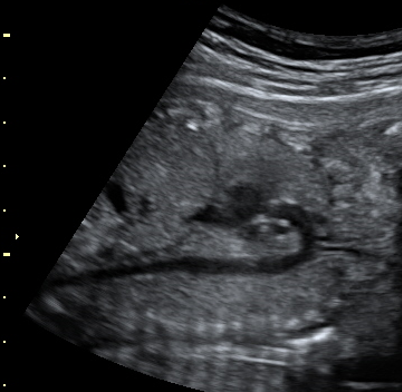

ACの断面から胎児尾側にスライドし、臍輪部や膀胱を確認。臍帯動脈が2本であることの確認も行う。